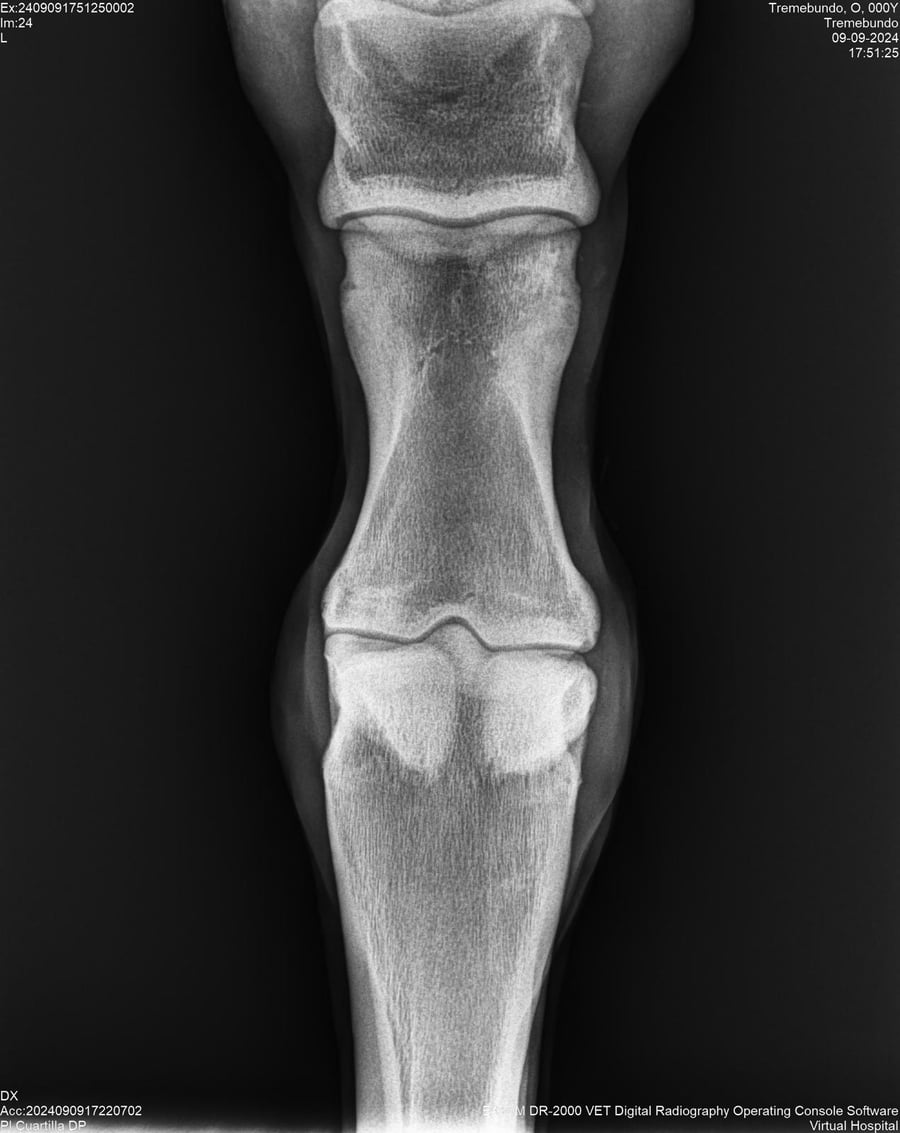

LOTE 37, TREMEBUNDO

Ficha del Lote

Identificador: #291140-

Generacion 2022